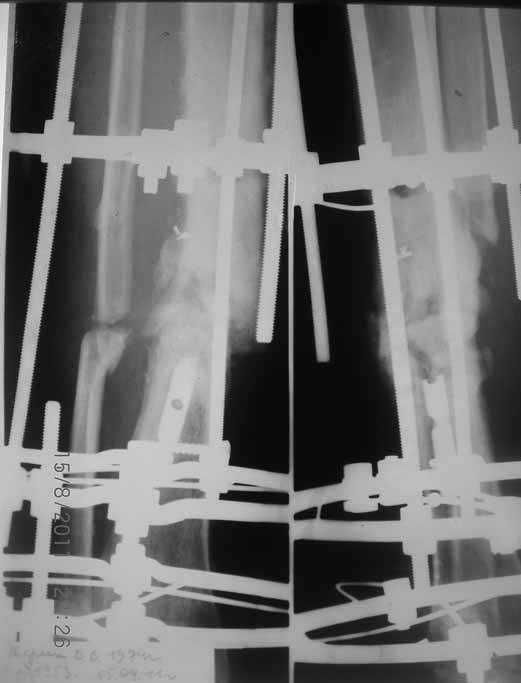

Примерная ситуация. Пациент 37 лет. Синтезировали где-то пластинкой. Попал к нам через 2 месяца.

19 апреля убрали через проколы пластину с винтами, пересекли fibula, наложили аппарат.

Немного потянули по оси, убрали вальгус, ротацию. 22 апреля (на 3-е сутки) заштифтовали окончательно. 29 апреля выписали из отделения. На все ушло 10 дней.

С уважением, Никита Заднепровский